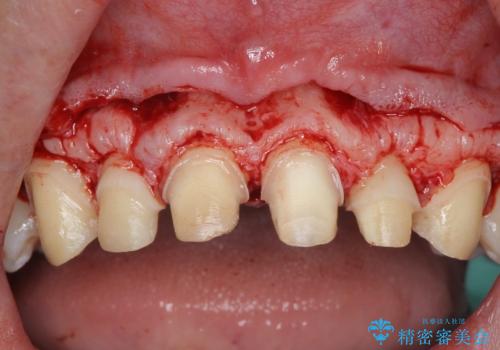

ただ、白いオールセラミッククラウンを製作・装着するのではなく、将来にわたり安定した状況を獲得するため、歯周外科を行い歯ぐきと周囲の歯槽骨の形態を整えていきます。

歯周外科を行ったことで、歯ぐきの形態や腫れが改善され、審美性だけでなく清掃性も大きく改善することができました。

外科処置の注意事項(リスク・副作用など)

- 外科手術のため、術後に出血、痛みや腫れ、違和感を伴います